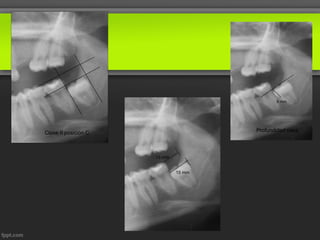

9 mm

Clase II posición C                   Profundidad osea

13 mm

15 mm

9 mm Clase IIposición C Profundidad osea 13 mm 15 mm